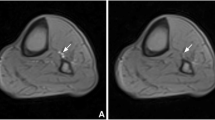

CMR imaging workflow. a Ischemia via arterial occlusion was induced in the lower extremity with an occlusive cuff tied around the middle of one thigh. The axial image slice was acquired at the widest part of the lower extremity. Four experimental statuses are defined as follows: baseline (Pre), cuff compression with a pressure of 20 mmHg above systolic pressure (Cuff-20), cuff compression with a pressure of 40 mmHg above systolic pressure (Cuff-40) and recovery period (Post). b T1-weighted anatomical images allow for the accurate delineation of muscle groups (1 = anterior, 2 = lateral, 3 = soleus, and 4 = gastrocnemius) in the lower extremity

Regions of interest (ROIs) were manually drawn on T1-weighted images around the 4 muscle groups (anterior, lateral, soleus, and gastrocnemius) at the largest cross-sectional area of the calf on both the experimental and control sides (Fig. 1). Attention was given to exclude areas influenced by bones and large vessels, and the inter-osseous muscle was not investigated because it contains a relatively large number of vessels [22]. ROIs were then copied and pasted into the corresponding functional perfusion maps. Average values within ROIs were recorded. Independent analysis of perfusion maps (from 7 randomly selected healthy subjects) by 2 radiologists blinded to the clinical outcomes was conducted to evaluate the interreader reproducibility. In addition, the repeat scans of 5 healthy subjects were analyzed by the same blinded radiologist to test the interscan reproducibility. Normalized values were obtained by dividing each imaging parameter value obtained under the experimental statuses (Cuff-20/Cuff-40/Post) by the baseline measurement (Pre).